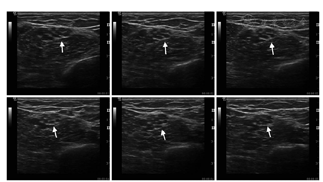

利用线阵探头沿着颈动脉先横断面、再纵断面扫查(图1A,图1B,图1C),记录二维显像、彩色血流显像及频谱多普勒图像,实时调节仪器参数以使图像质量显示清晰;患者较胖、两侧VA开口及左侧SA显像不理想时,可选用低频线阵探头或凸阵探头。